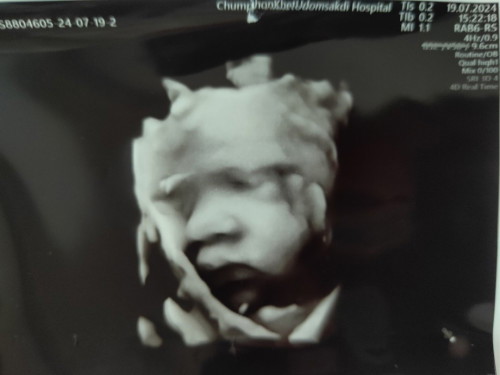

30+5วิค น้องยังไม่กลับหัวเลย

วันที่19/7หมอนัดคุณหมอซาวด์ไห้น้องน้ำหนักตอนนี้2157คุณหมอบอกว่าน้องตัวใหญ่นะค่ะน้องยังไม่กลับหัวเลยน้องอยุ่ท่านั่งเอาก้นลงอยากถามแม่ๆว่าน้องกลับหัวตอนกี่วิคกันค่ะ